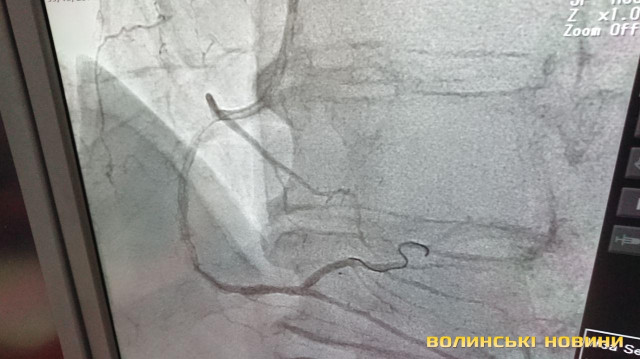

З 2013-го року реперфузійні центри працюють за системою «24/7», тобто ми допомогу надаємо у будь-який час і кожного дня. З 2018 року до цієї роботи долучився реперфузійний центр у м. Ковель завдяки ангіографу, встановленому за кошти субпроекту Світового банку. У нашому центрі щодня маємо 3-5 процедур. Також почали проводити тромбоекстракцію у пацієнтів з ішемічним інсультом. Це складна процедура, яку роблять у небагатьох клініках України. Суть у тому, що при інсульті треба вчасно відкрити судинку. У судину заводиться спеціальне обладнання і проводяться маніпуляції із видалення тромбу. Є випадки, що молодим людям ставало значно краще.